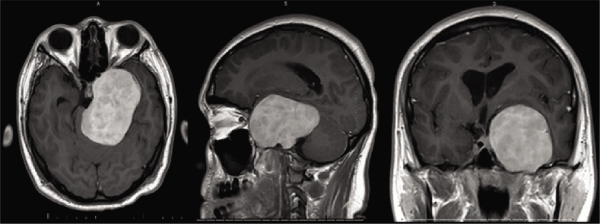

为了进一步评估,进行了头部的计算机断层扫描血管造影术(CTA)和有和没有对比的磁共振成像(MRI)。CTA显示颞骨左侧蝶骨和岩骨部分的骨重塑,与左侧颈内动脉海绵体段和岩骨段受到外部压迫(约50%变窄)相关。【 图2 】。脑部核磁共振显示一个5.2 × 7.8 × 5.1厘米的不均匀轴外强化肿块,位于左侧颞中区,累及颅底和左侧卵圆孔、圆形和棘突,左侧颈内动脉被包裹并中度狭窄,轻度梗阻性脑积水,脑干明显受压【 图3 】。此外,左咀嚼肌萎缩与左下颌体和下颌支发育不全有关【 图4 】。

图3:术前磁共振成像图描述:对比T1加权磁共振成像与5.2 × 7.8 × 5.1厘米的轴向、矢状和冠状视图,不均匀的轴外增强肿块位于左侧颞中区,累及颅底和左侧卵圆孔、圆形和棘突,左侧颈内动脉被包裹和中度狭窄,轻度梗阻性脑积水,脑干明显受压。